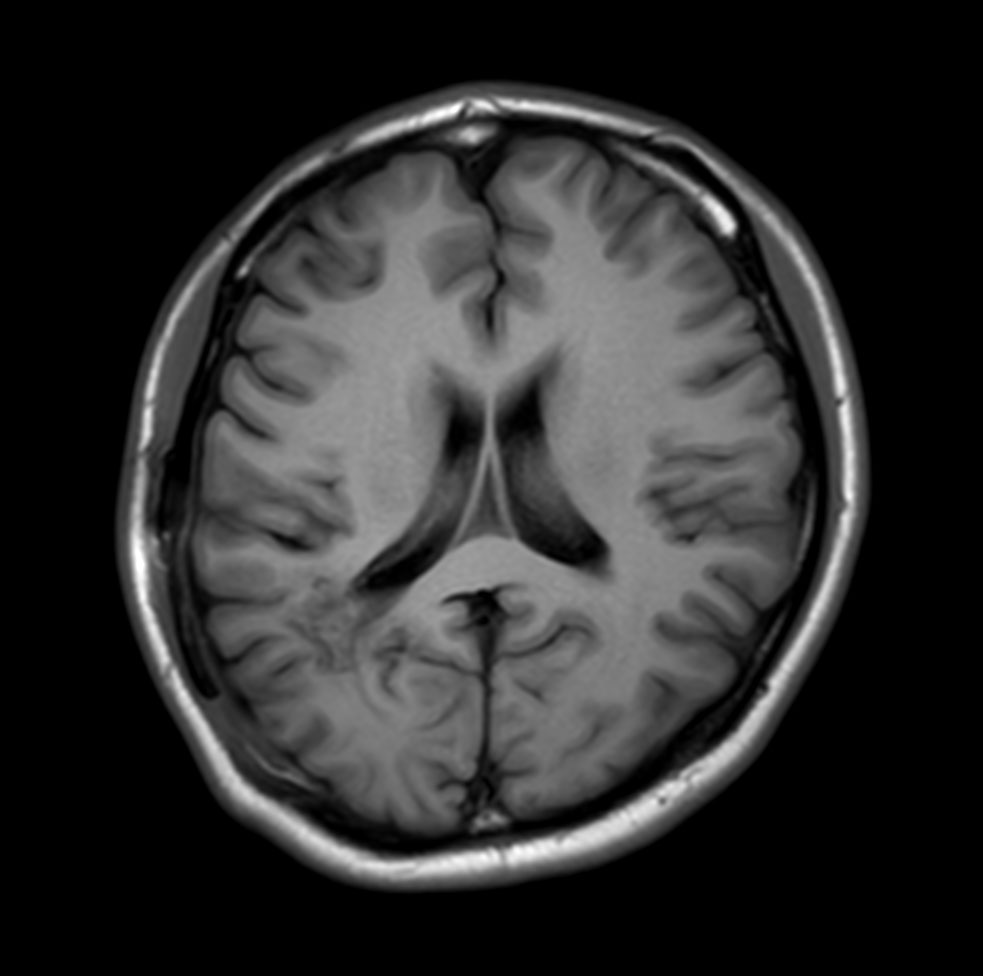

Axial T1w IR TSE